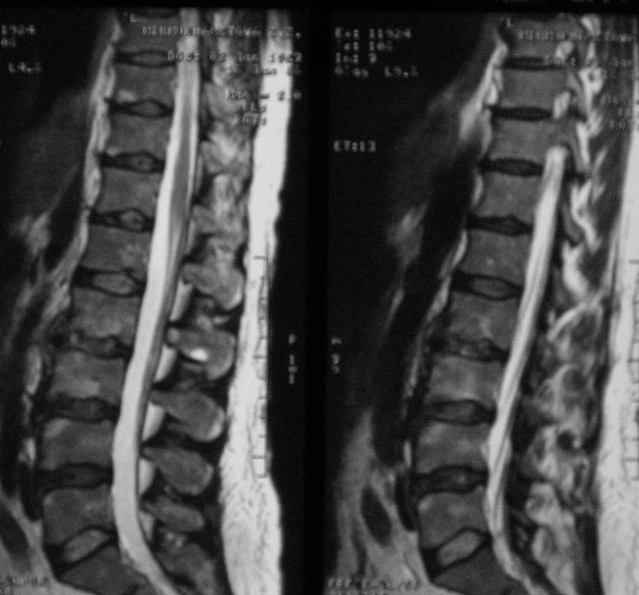

Отправляю MRI в динамике, снятые с пленки на фотоаппарат.

|

MRI через три недели

По данным представленных КТ и МРТ у больной имеется достаточно выраженная степень деструкции тел позвонков (около 30% общей костной массы тела позвонка), что определяет высокий риск возникновения патогических переломов и появления локальной кифотической деформации на этом уровне.